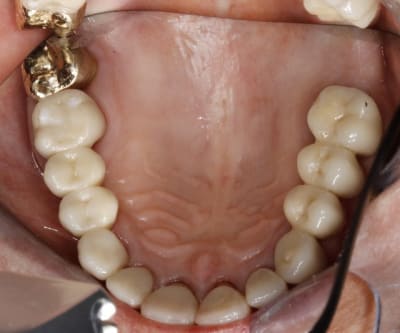

petit contrôle à 8 jours, vérification occlusion et latéralité (désocclusion canine.

très légère retouche esthétique (latérale, centrale et canine)

et élimination d'un petit résidu de ciment sur 27 (1mm2)

je prefere le coté droit au coté gauche ,au niveau des 6 et 7 .

tu me crois si je te demande de gratter un poil la pointe des cuspides de 26 et 27 et surtout en en distal de 27 ? et puis un peu 16 et 17 ( surtout 17 )ca mange pas de pain !

non seulement je te crois (cette fois) mais je l'ai déjà fait,(avec un mini éclat sur la cuspide vestibulaire de 15) pas assez sans doute, mais je préfère retoucher en plusieurs fois.

tu vois , dans le cas de la photo :

il n'ya pas un fort calage lateral dans les trajets de fermeture sur 14+15 .du coup j'ai laissé un leger jeu sur la canine .

par contre si j'avais eu un calage fort sur 14+15 , j'aurais du surforcer au niveau canine .parce que le support desmondontal de la canine est supposé etre meilleur et supposé sur guider les pm.

donc dans ton cas , la 16 etant un implant avec un fort calage lateral , il te faudrait un super- super guide canin pour compenser . or le support paro de ta patient n'etant pas capable de le supporter , ne serait il pas plus simple de donner de l'aisance à l'arriere ?

alors qu'avant ,elle etait bloquée à droite ( un coup de brigitte ? ), et elle avait decompensé a gauche . tu vois les pointes 25+26 etc ?

le fait d'avoir diminué le recouvrement a droite , a permis d'augmenter l'engrènement à gauche ( ça se voit bien sur la photo du cas fini )